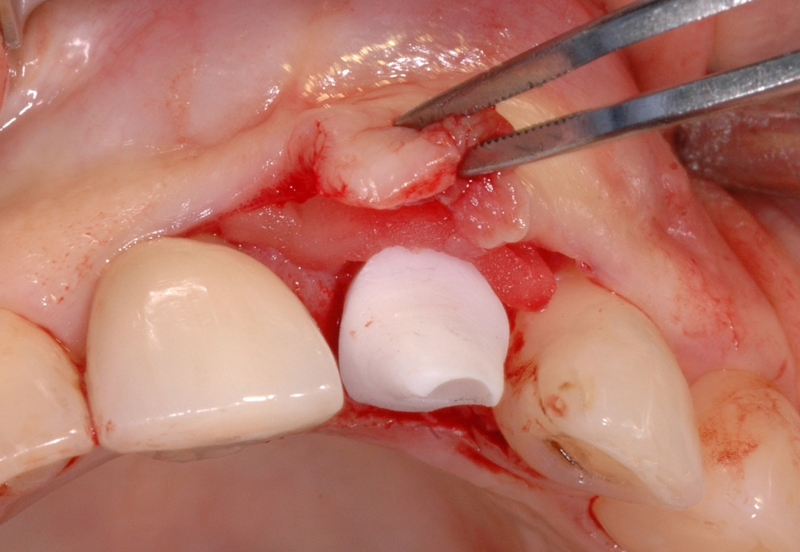

4/18 - Clinical situation, occlusal viewGBR together with soft tissue augmentation with mucoderm® and maxresorb® - Dr. S. Scherg